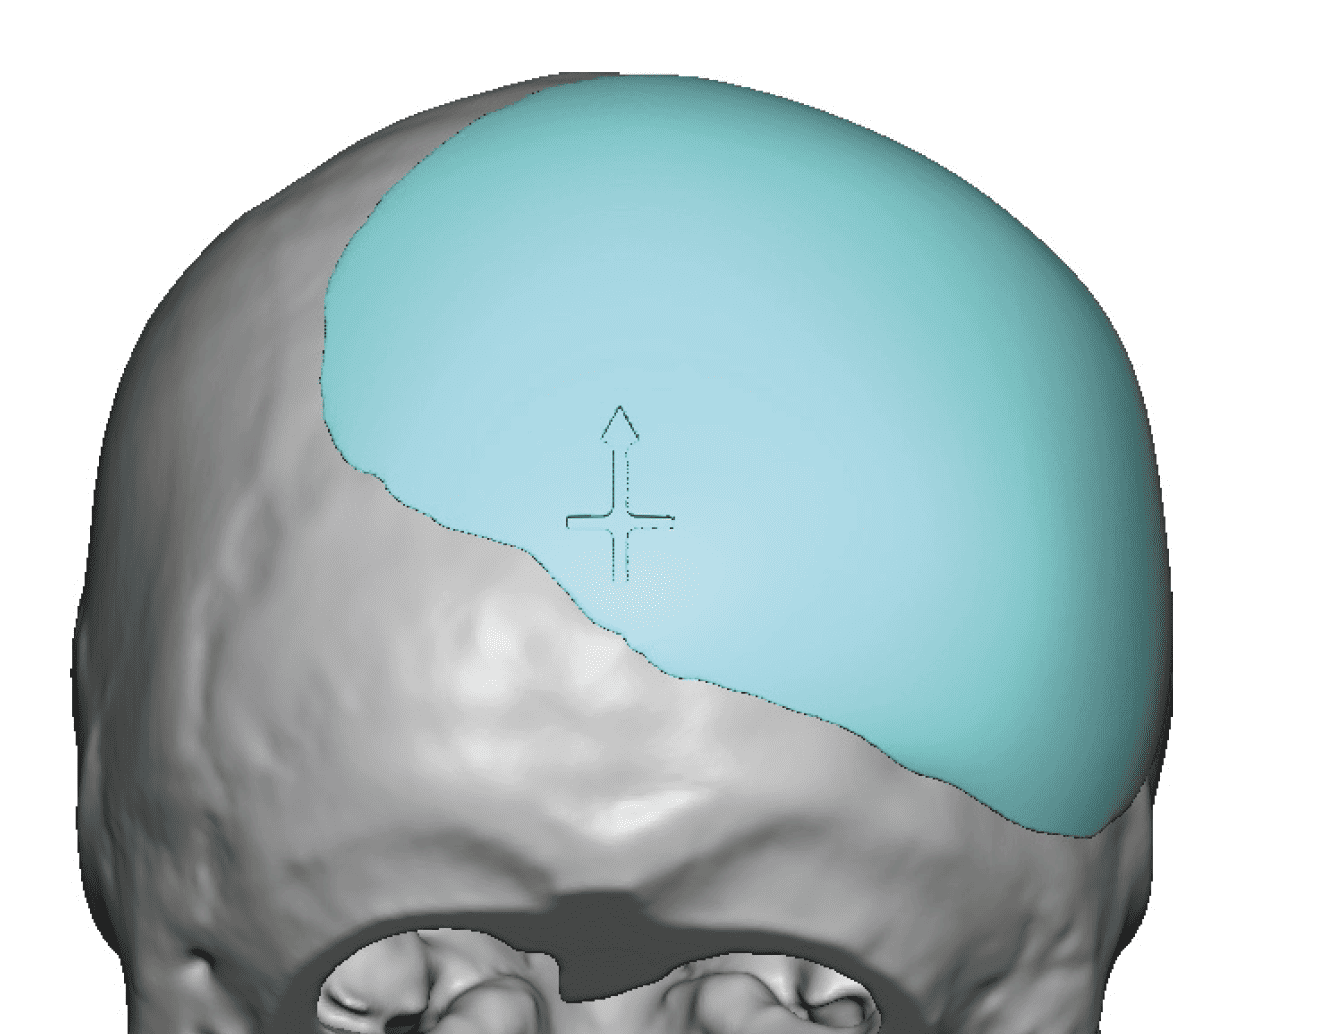

Patient 28

Desire for rounder shape to the top of the head from a congenital parasagittal deficiency skull shape.

Custom skull implant designed to fill in the parasagittal deficiencies.

Desire for rounder shape to the top of the head from a congenital parasagittal deficiency skull shape.

Custom skull implant designed to fill in the parasagittal deficiencies.